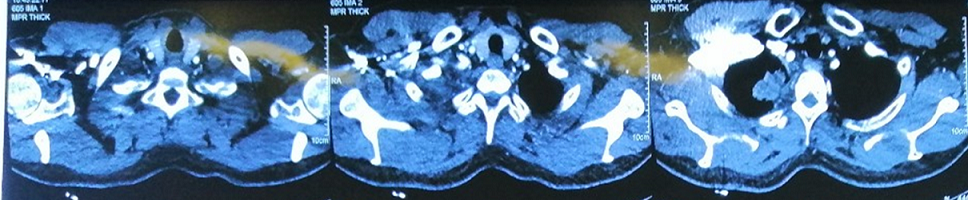

– Chụp cắt lớp vi tính lồng ngực:

Hình 1: Hình ảnh chụp cắt lớp vi tính lồng ngực: Hình ảnh khối u thùy trên phổi phải kích thước 5x6cm, hạch trung thất, rải rác tổn thương thứ phát hai phổi (Mũi tên màu đỏ).

Chụp cắt lớp vi tính lồng ngực sau điều trị: Hình ảnh khối u thùy trên phổi phải kích thước 3×2 cm

So sánh trước và sau điều trị:

Trước điều trị: Hình ảnh khối u thùy trên phổi phải kích thước 5x6cm

Sau điều trị 6 tháng: Hình ảnh khối u thùy trên phổi phải kích thước 3×2 cm